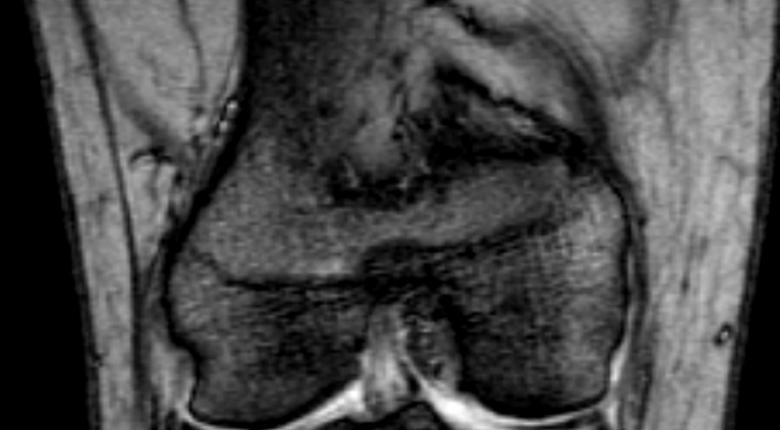

간단히 말하면 MRI 촬영은 주로 뇌, 척추, 근육·골, 관절질환 등의 촬영에 주로 사용됩니다. 단순히 뼈를 찍는 엑스레이와는 다르며 근육이나 관절, 신체 내부 등을 섬세하게 촬영할 수 있는 검사입니다. 개복을 하지 않고도 마치 어떤 상태인지 알 수 있는 장비이므로 1회 촬영 가격이 비쌉니다.

실제로 MRI 검사를 무릎 관절 때문에 촬영을 했을 때, 의사가 촬영된 영상을 보고 반월상연골판 손상이라는 정확한 진단명을 내려주더군요. 이처럼 MRI 촬영은 진단에 큰 도움이 됩니다.